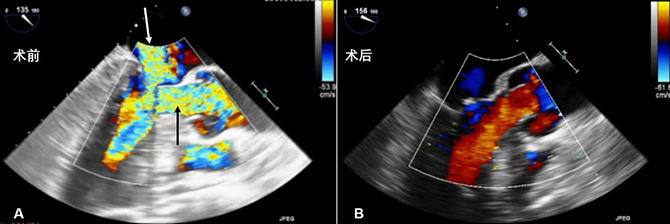

胸腔镜所带来的微创效果不仅是切口的美观,还有术中输血量、术后切口并发症发生率的下降,这也消除了很多患者对正中开胸的恐惧。而且,手术的安全性大大提高。目前该团队已完成3例手术,术后患者左室流出道梗阻完全解除、二尖瓣反流消失,无室间隔穿孔及完全房室传导阻滞的发生(图4)。

图4. A.术前经食管超声下可见左室流出道高速血流(黑色箭头所指处)及二尖瓣中量反流(白色箭头所指处)

B. 术后经食管超声可见左室流出道通畅,无二尖瓣反流。